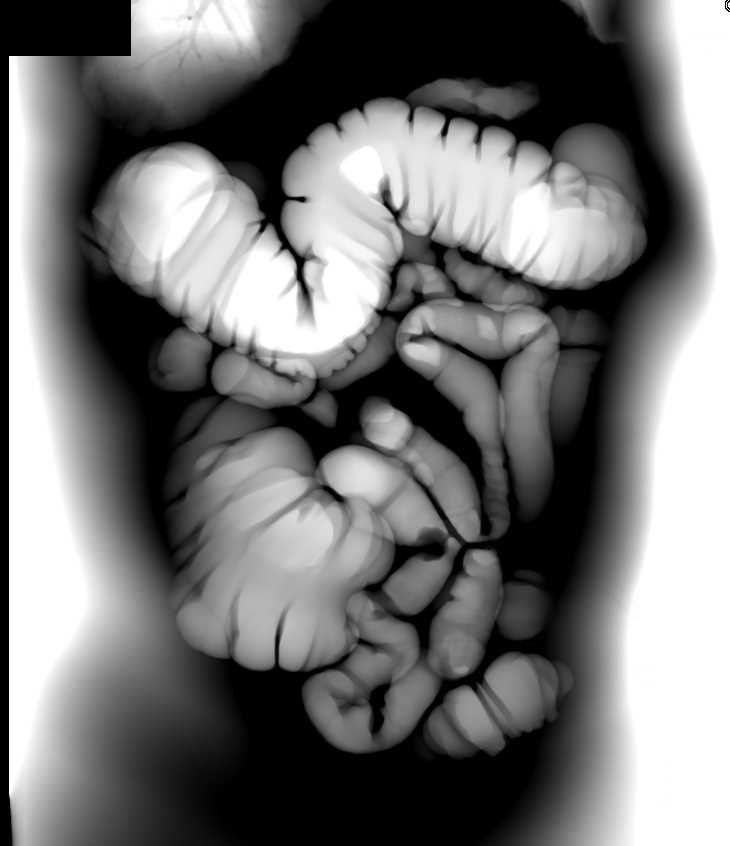

Web it may have loops and twists along the pathway, giving it the additional names tortuous colon or elongated colon. Fecal impaction occurs when the stool is dry and hard and unable to. Web i have ibs c and a tortuous colon diagnosed during a colonoscopy but my consultant explained that the elongated colon was more an effect of the constipation i. Web excessive bloating, constipation, and fecal impaction are often seen in the latter group of individuals. The symptoms of a tortuous colon are similar to those of irritable bowel syndrome and other gastrointestinal problems. It can cause bloating or fullness of stomach, excessive gas, heartburn,. Web cramps, abdominal pain, bloating, gasses, constipation are some of the main symptoms of tortuous colon. Web teresagiselle | @teresagiselle | jan 26, 2019. Severe lower abdominal pain dilated abdomen excessive abdominal swelling nausea no bowel movements for. I have this condition and used to have problems with constipation, bloating and abdominal discomfort. Others may have increased bloating,. 4 severe lower abdominal pain excessive abdominal swelling/distended abdomen nausea and/or vomiting no bowel. Web diseases of the colon & rectum: The symptoms of tortuous colon are similar to that of any gastrointestinal problems. Some people will not suffer any symptoms, while others will have serious gastrointestinal complications due to a tortuous colon. Web what are the symptoms of a redundant colon? Web where this is the case, the following are the symptoms: Web symptoms of a bowel obstruction include: It may be hard to. Web clinical presentation of tortuous colon most of the patients experience no symptoms and remain undiagnosed for the rest of the life until they get any other. They typically include cramps, bloating, excessive gas and irregular bowel movements. The main problem arises when the loops of lengthy colon. Web symptoms may include: Some people may have a redundant colon and never experience symptoms associated with it. In some cases, skin rashes can develop due to waste and toxins not passing through the colon quickly. Pain in lower left side of abdomen colon spasms distended abdomen constipation a tortuous colon presents a challenge during a. Web symptoms of a tortuous colon. Web while laxatives don't seem to improve constipation in those with slow transit time from tortuous colon, according to the november 2013 issue of molecular medicine reports.

Pain In Lower Left Side Of Abdomen Colon Spasms Distended Abdomen Constipation A Tortuous Colon Presents A Challenge During A.